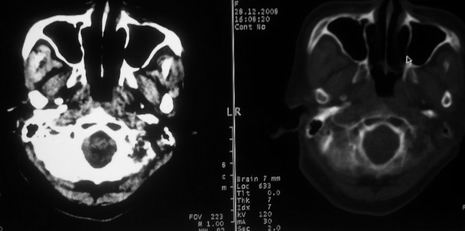

女,72岁,头晕。额骨有无问题。

额骨呈磨玻璃状增厚,考虑骨纤。

额骨呈磨玻璃状增厚,考虑骨纤

骨纤维组织异常增殖症又名纤维性骨炎,是一种以骨纤维变性为特点的骨胳系统疾病,是否为一真性肿瘤尚无定论。该病好友于儿童及青年,女性较多见,60%发生于20岁以前,偶见于婴儿和70岁以上老年人。男女发病为1∶2。80%以上表现为病骨区畸形肿胀;建议祥问病史,时间?